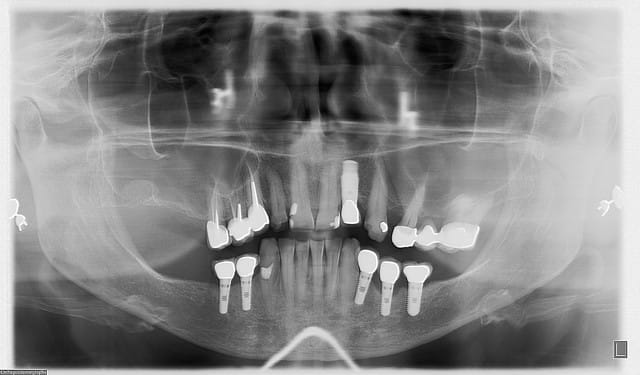

l'implant en 22 va bien, l'image est bizarre du fait de son angulation...et s'il parait bien gros...c'est qu'il est bien gros (un 4.7/16!!!) car posé en EII et la racine de la 22 était énorme...

en 44/45 tout va bien, 34 lui aussi, 36 pas trop mal....mais 35!!!

bizarre quand même, j'ai sondé, pas de perte en lingual mais perte de 3mm en vestibulaire...

je l'ai mise sous AB, fait un bon nettoyage/aéropolissage, dit de bien reprendre l'hygiène, et rdv pour contrôle dans un mois...